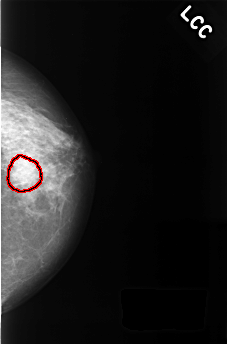

FILE: C_0426_1.LEFT_CC.OVERLAY

TOTAL_ABNORMALITIES 1

ABNORMALITY 1

LESION_TYPE MASS SHAPE IRREGULAR MARGINS SPICULATED

ASSESSMENT 3

SUBTLETY 2

PATHOLOGY BENIGN_WITHOUT_CALLBACK

TOTAL_OUTLINES 1

BOUNDARY

LEFT_CC LINES 4472 PIXELS_PER_LINE 2944 BITS_PER_PIXEL 12 RESOLUTION 50 OVERLAY